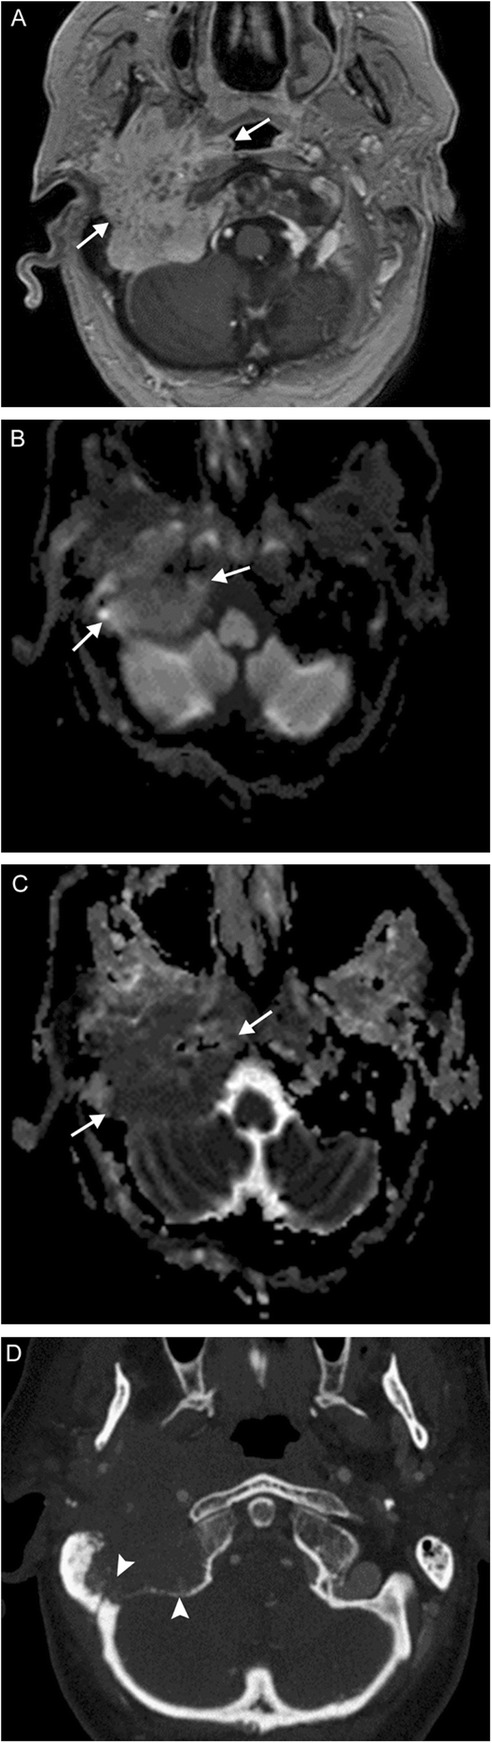

Fig. 12.

Jugulotympanicum paraganglioma. A 49-year-old woman with voice change and pulsatile tinnitus. Coronal T2-weighted MR images (a, b) and axial contrast-enhanced T1 image (c) demonstrate a T2-hyperintense, enhancing mass centered at the left jugular bulb (white arrows) extending into the hypotympanum (white arrowhead). Axial CT of the temporal bones (d) reveals abnormal soft tissue in the left middle ear (black arrow) with osseous 'moth-eaten' destruction at the jugular foramen (black arrowhead); the cochlear promontory in preserved (not shown). Based on location and appearance, findings are consistent with a jugulotympanicum paraganglioma (glomus jugulotympanicum tumor)